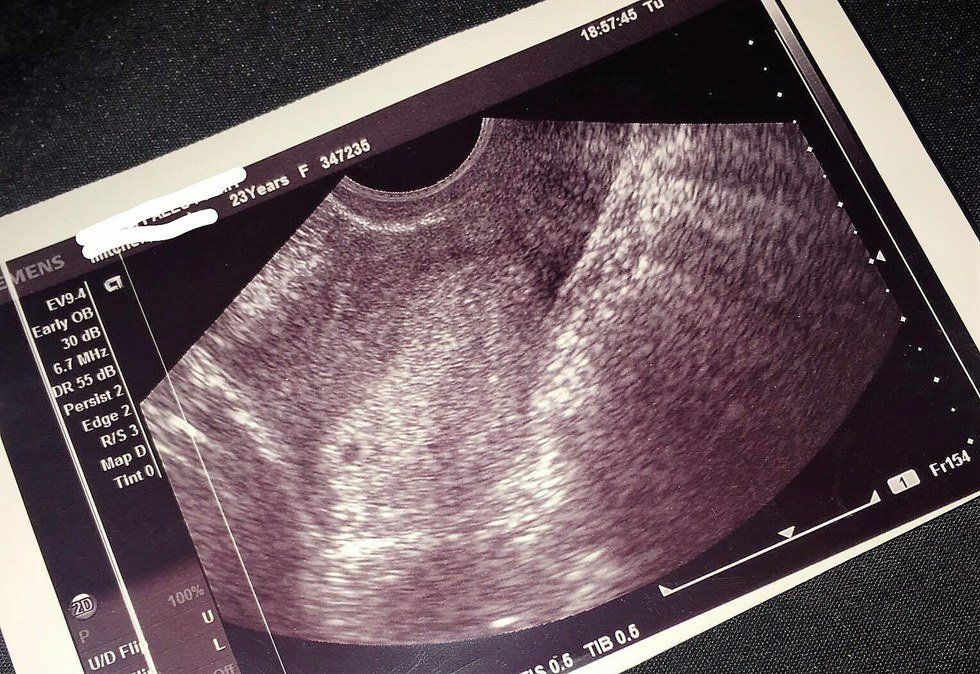

So I went to a pre-screening and met with a counselor at my local Planned Parenthood. We discussed my options at length. I was poked and prodded and given an ultrasound to confirm the pregnancy. The PA asked if I wanted a picture of the ultrasound and something within me did. And you know what that ultrasound showed? At 6 weeks, my pregnancy was a 4 millimeter cluster of cells. In fact, my pregnancy was so small, I had to undergo two trans-vaginal ultrasounds before they were able to locate it.